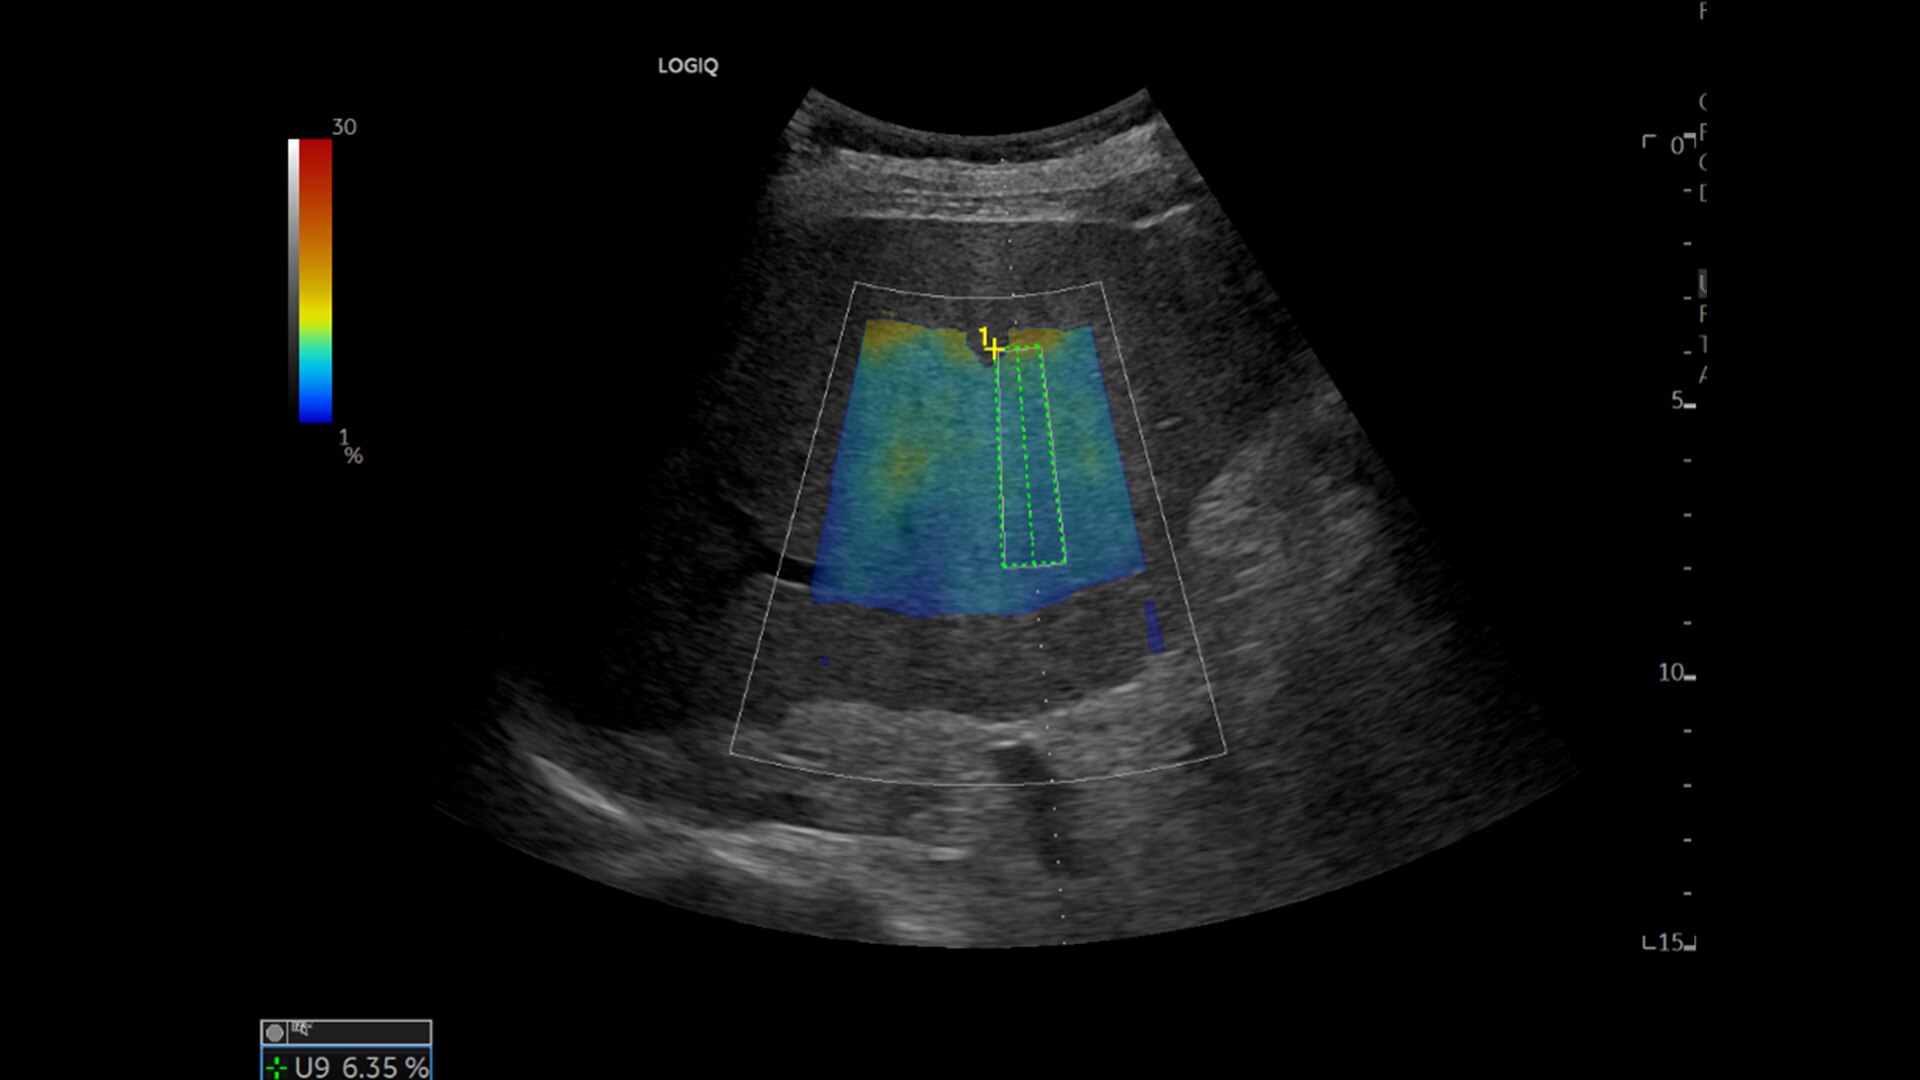

Le ayuda a evaluar enfermedades vasculares, desde enfermedades cardiovasculares y enfermedades vasculares periféricas hasta enfermedades vasculares pulmonares.

Ideal para imágenes superficiales de flujo en color, anatomía de la barbilla y la mandíbula, y otras exploraciones ecográficas utilizadas en procedimientos estéticos.